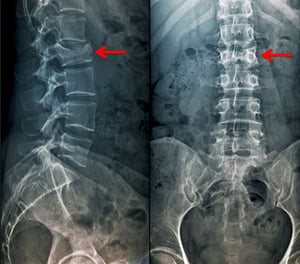

Questa frattura da compressione della prima vertebra lombare è visibile sulla vista anteroposteriore come una grave perdita di altezza e aumento della radiodensità.

ZEPHYR/SCIENCE PHOTO LIBRARY